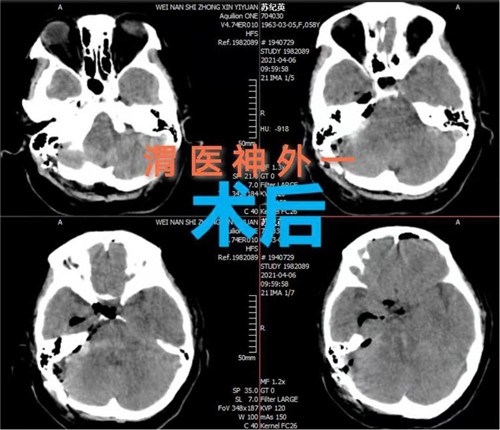

手术计划制定后,即刻安排手术,手术麻醉科确定了由麻醉医师钟永慧、配合护师党海婷和马丹组成的麻醉护理团队。手术历时近4个小时,手术过程患者生命体征平稳,术中总出血量约50毫升,术后患者恢复自主呼吸。术后次日患者生命体征平稳,意识恢复,右侧肢体活动正常,左侧肢体活动正在恢复中。